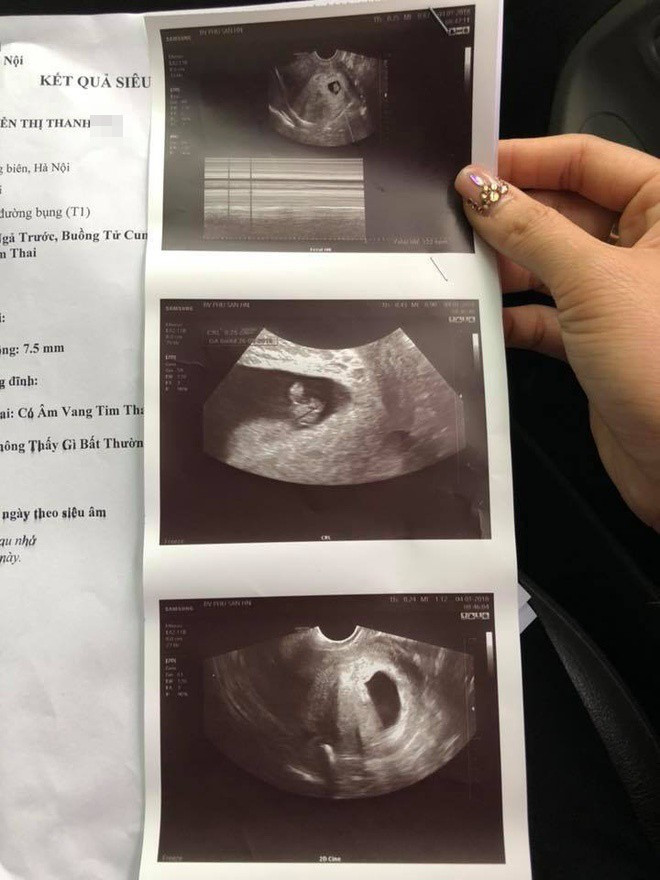

Kết quả siêu âm tại BV Phụ sản Hà Nội cho thấy thai nhi vẫn phát triển bình thường. Ảnh: Bệnh nhân cung cấp |

Khi chuyển sang Bệnh viện Phụ sản Hà Nội khám và siêu âm, kết quả siêu âm cho thấy thai phát triển bình thường.